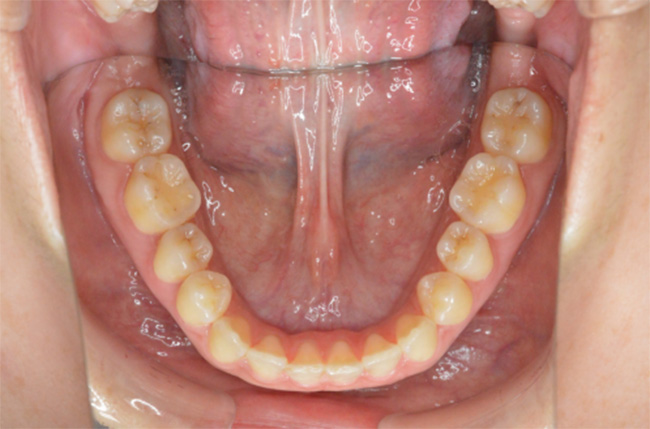

治療終了時